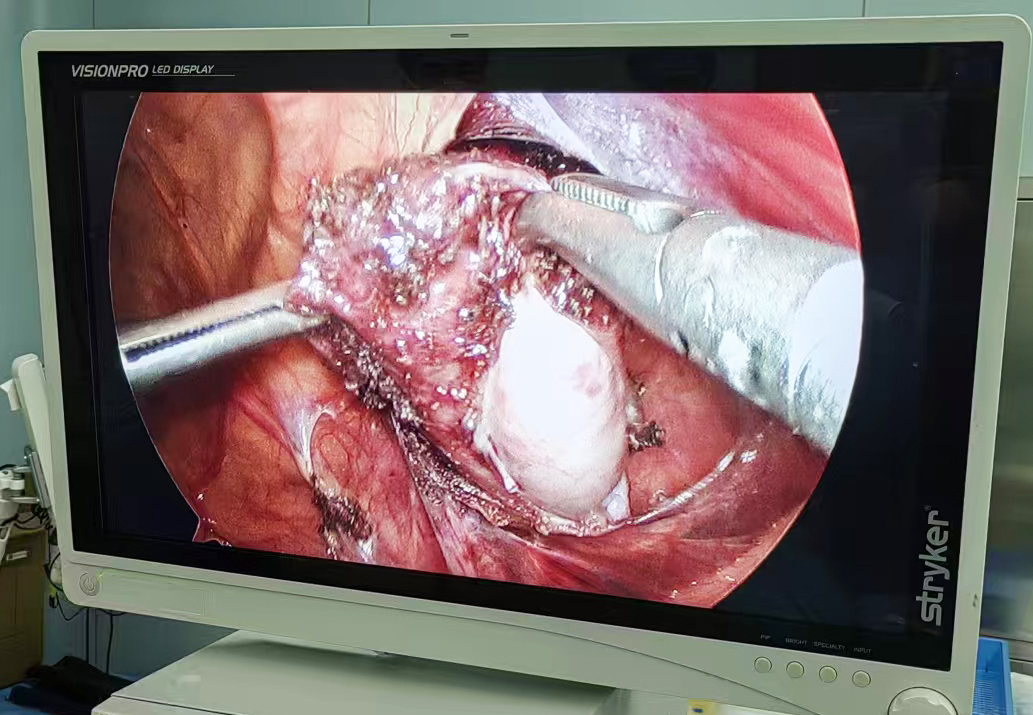

术中解剖并切除隐睾

手术由胸外科马南山医生主刀。团队首先顺利完成了左侧疝气的微创修补,后借助腹腔镜的视野优势仔细探查右侧腹股沟区,在右侧腹膜后区域精准定位未降的右侧睾丸,随后仔细游离并妥善处理精索血管及输精管,最终成功将隐睾切除并完整取出。整个手术仅在腹壁留下3个1cm左右的微小切口。患者术后恢复迅速,第1天即可下床活动和进食,术后第2天便顺利出院。